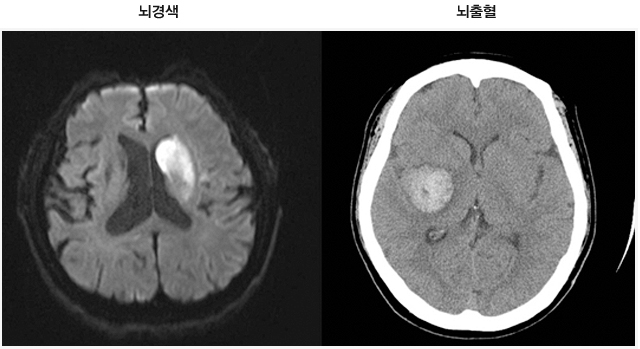

뇌졸중이란 뇌혈관의 이상에 의해 뇌혈관이 막히거나 터져 뇌의 국소 또는 전반적인 뇌 기능 장애를 일으키는 것을 말한다. 뇌경색은 크게 두 가지로 나뉜다. 뇌혈관이 막혀 뇌에 허혈성 변화로 인해 나타나는 뇌경색과 뇌혈관의 출혈로 인해 뇌에 피가 고이는 뇌출혈이다. 우리나라의 뇌졸중의 약 15%는 출혈성 뇌졸중이고, 나머지는 허혈성 뇌졸중으로 뇌졸중의 다수를 차지한다.

CT 검사는 뇌경색과 뇌출혈을 구분하고 특히 뇌출혈을 빠르게 감별 진단할 수 있다. 단, 뇌경색의 경우 일정 시간이 지나야 병변이 보이기 때문에 초기에 CT 검사로 진단하기 어렵고, 뇌출혈은 출혈 발생 후 CT에 바로 나타나기 때문에 뇌출혈 진단에 유용하다.

뇌경색 부위와 뇌혈관의 협착 및 폐쇄 여부를 확인할 수 있다. CT에 비해 뇌출혈 진단 능력은 비슷하나 초기 뇌경색 및 범위가 작은 뇌경색 등도 진단이 가능하다. 단, 검사 시 금속성 물질을 부착한 (인공 심박기 등) 경우 검사의 어려움이 있다.